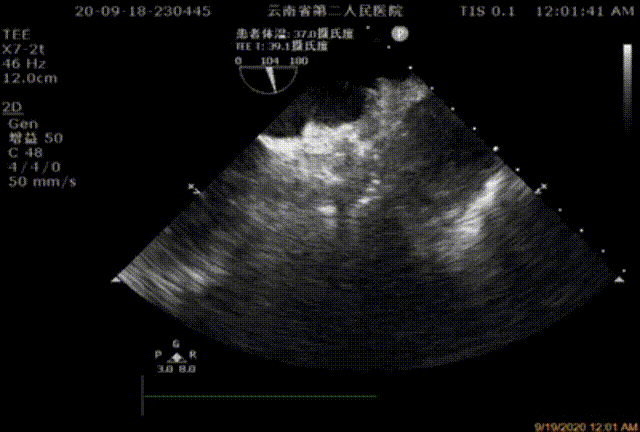

TEE

将传输外鞘推送至左心耳开口,结合术前及术中超声检测结果,选择直径26mm左心耳封堵器。严格排气后送入左心耳封堵器,在食道超声及DSARA30°+CAU20°透视下精确定位左心耳封堵器固定盘,造影示位置及封堵良好,透视下释放封堵盘并牵拉,造影及超声检测未见明显漏肩及侧漏,固定盘及封堵盘稳定,贴合左心耳开口好。